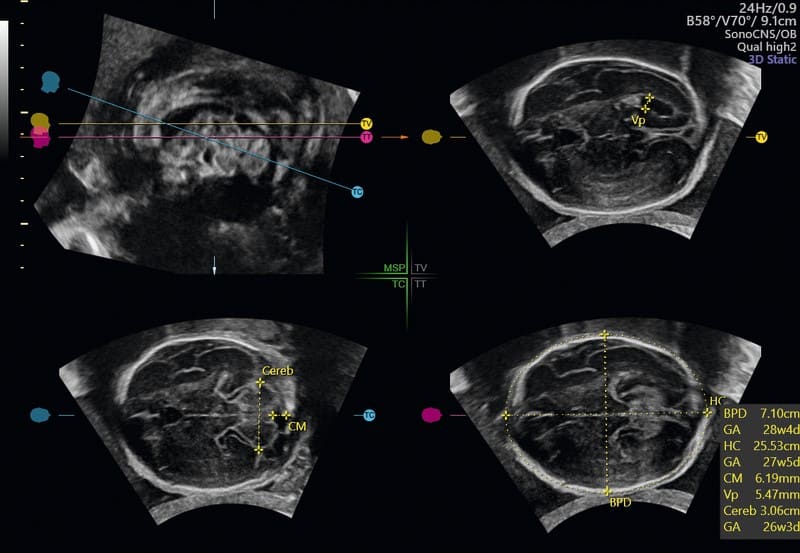

SonoCNS: tool semiautomatico per allineare e visualizzare correttamente le scansioni consigliate nei piani TV (trans-ventricolare), TT (trans-talamico), TC (trans-cerebellare), unitamente alle misurazioni del cervello fetale, utilizzando la tecnologia di deep learning GE Healthcare partendo da un’unica acquisizione 3D.